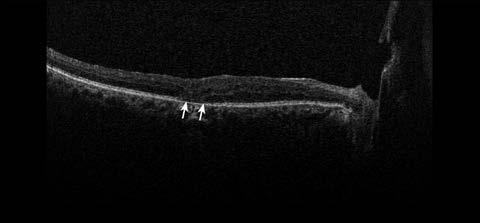

Los cambios patológicos más específicos, como la desorganización de las capas internas de la retina (DRIL; Figura 1), solo pueden apreciarse mediante OCT y se han identificado como marcadores del potencial visual y predictores de la progresión de la RD.4 Del mismo modo, la alteración de la retina externa (Figura 2) y el daño temprano de los fotorreceptores pueden indicar una enfermedad más avanzada con un pronóstico visual desfavorable.5

Figura 2. Tomografía de coherencia óptica de un paciente de 59 años con antecedentes de retinopatía diabética proliferativa que muestra una alteración de la retina externa (flechas).